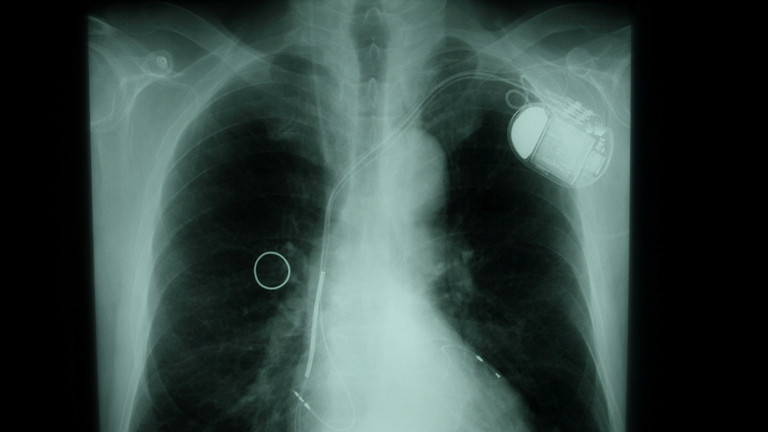

Для этого вам предложат специальное кардиоустройство, например, кардиостимулятор, дефибриллятор, кардиоресинхронизатор (СРТ) или искусственное сердце (левый искусственный желудочек). В 2018 году центр сердечно-сосудистых заболеваний клиники Альбертинен первым в Гамбурге был сертифицирован как межрегиональный центр аппаратного лечения сердечной недостаточности.

Имплантация кардиостимулятора: однокамерного, двухкамерного, трехкамерного (СРТ), беспроводного (безэлектродного)

Имплантация дефибриллятора: однокамерного, двухкамерного, трехкамерного (СРТ), подкожного (S-ICD)